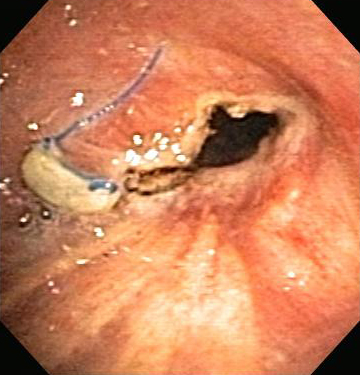

Golden-S or reverse S-sign on chest CT (left image) traced by yellow line. Flexible bronchoscopy (right image) shows the central obstructive lesion at the left mainstem bronchi.

From the collections of Jose Fernando Santacruz MD, FCCP, DAABIP and Erik Folch MD, MSc; used with permission